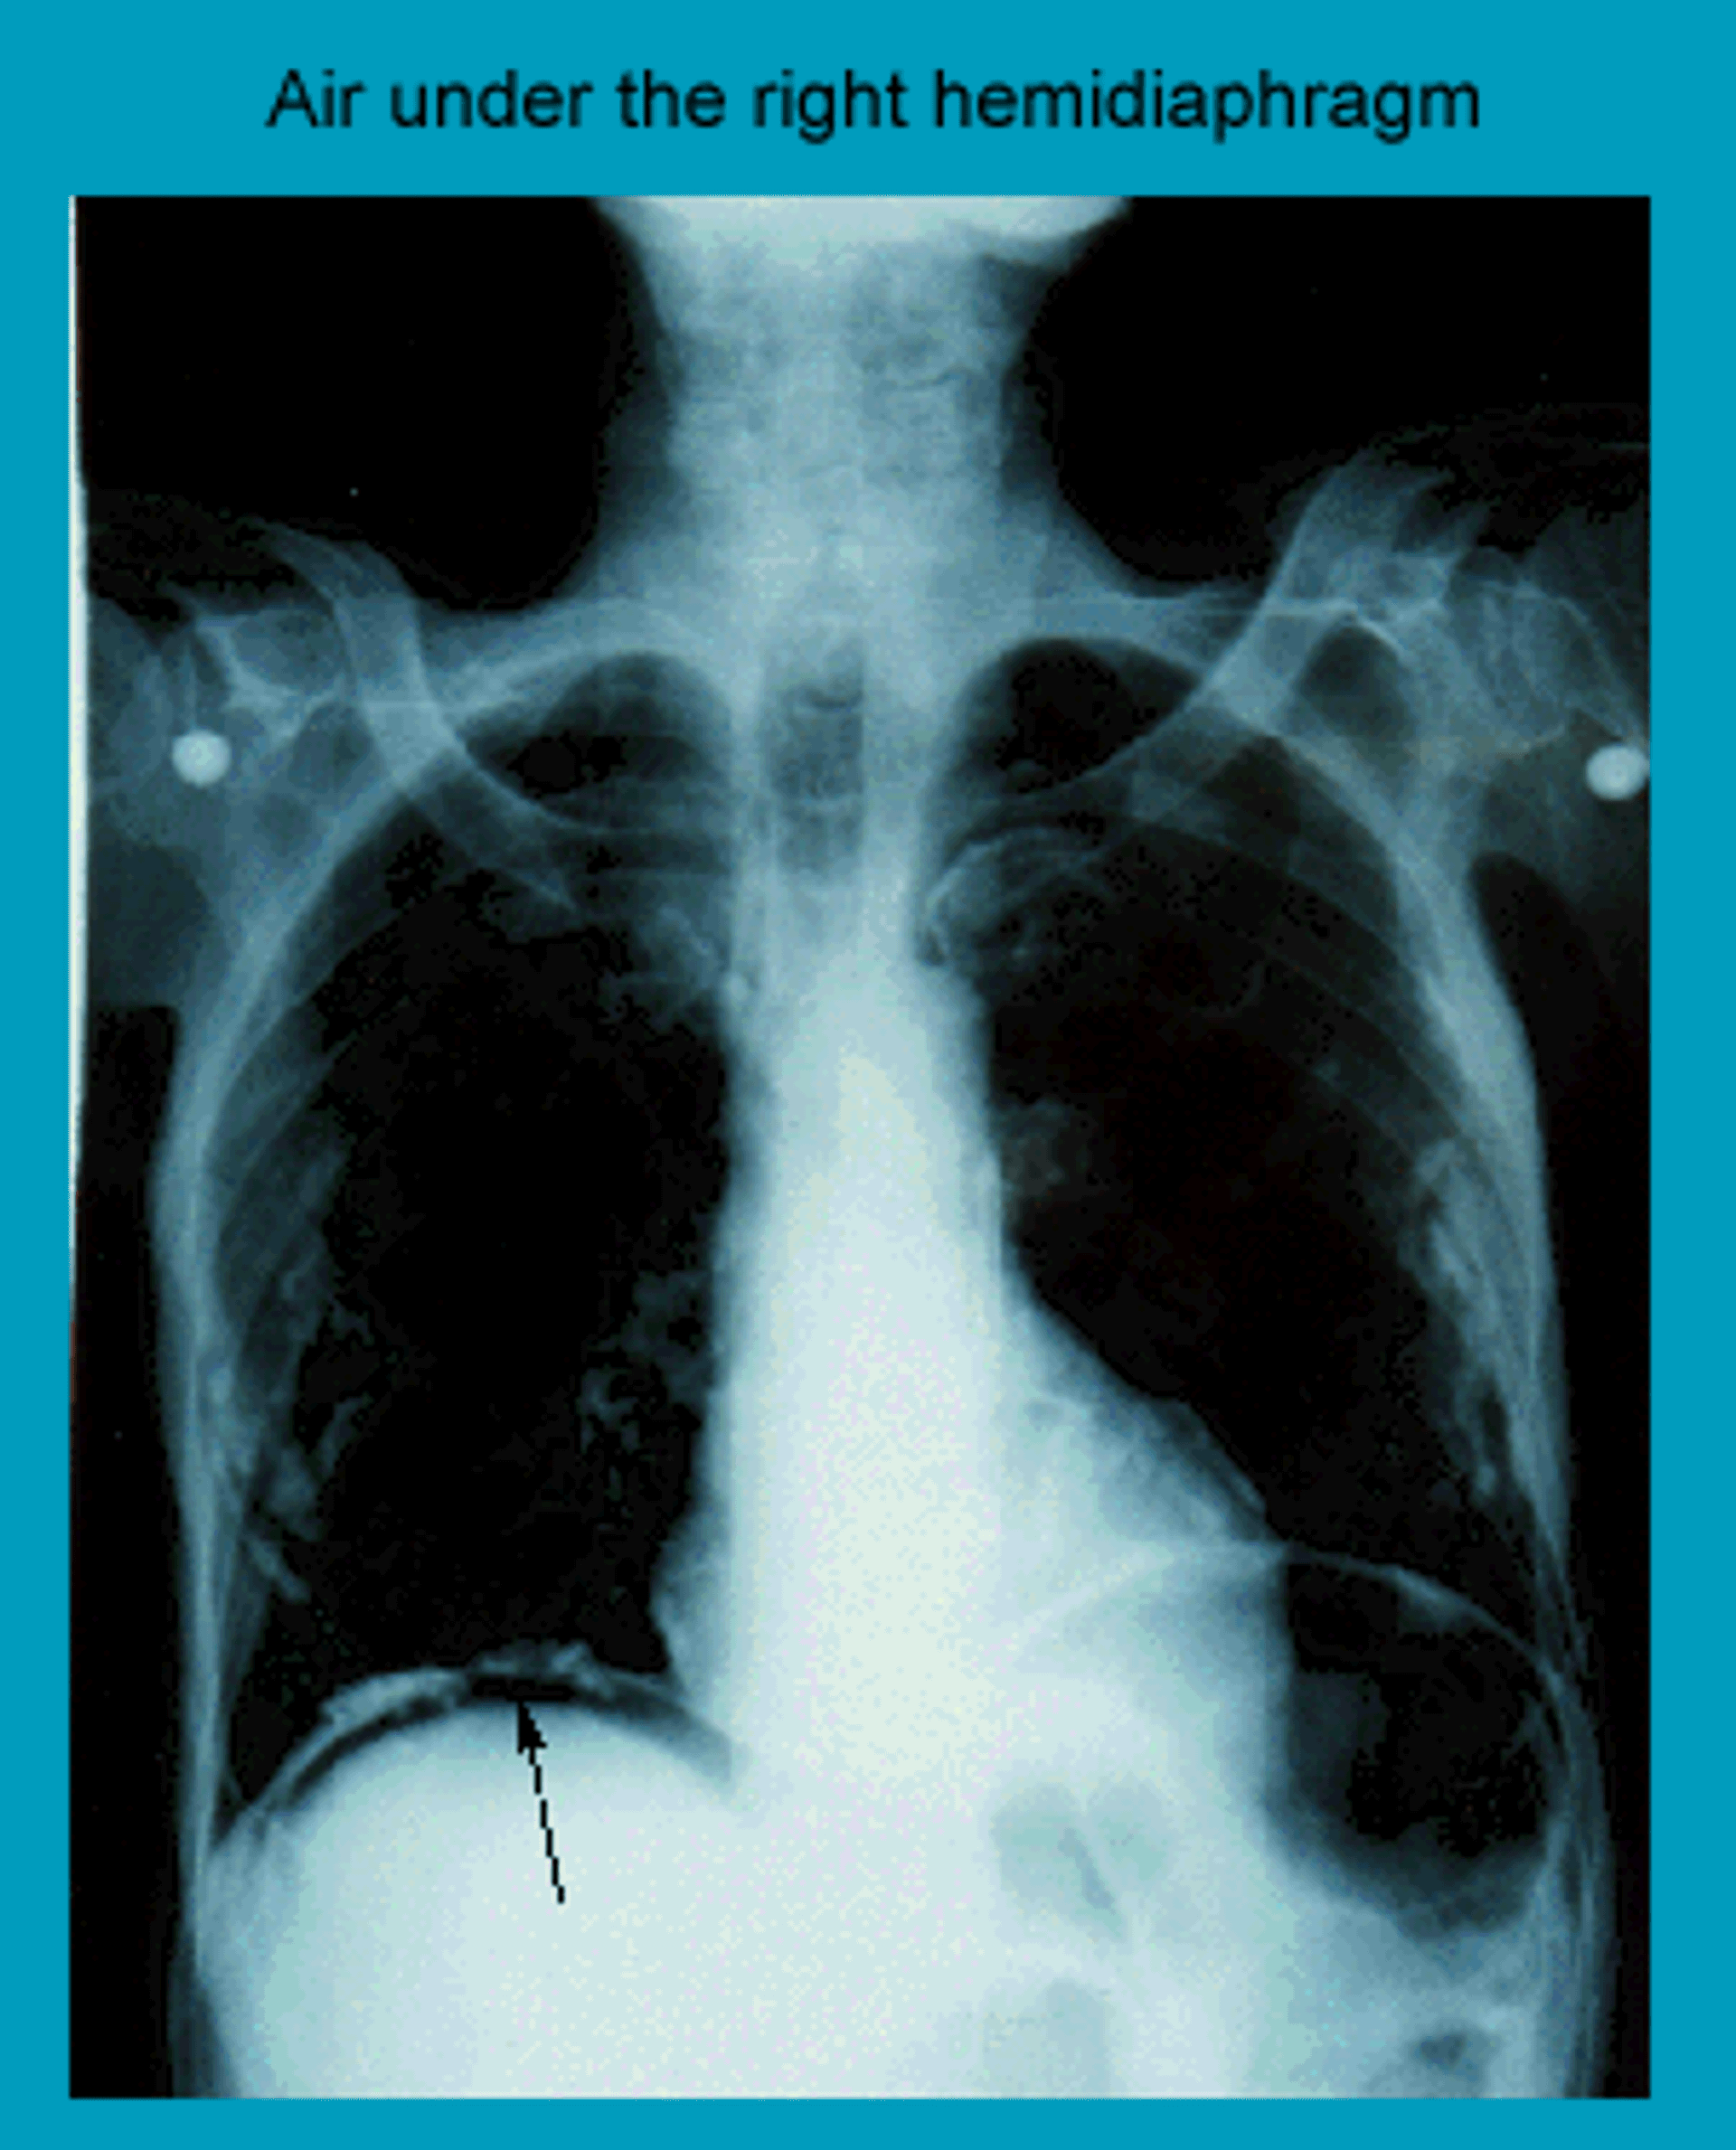

Aire bajo el diafragma en la radiografía de tórax